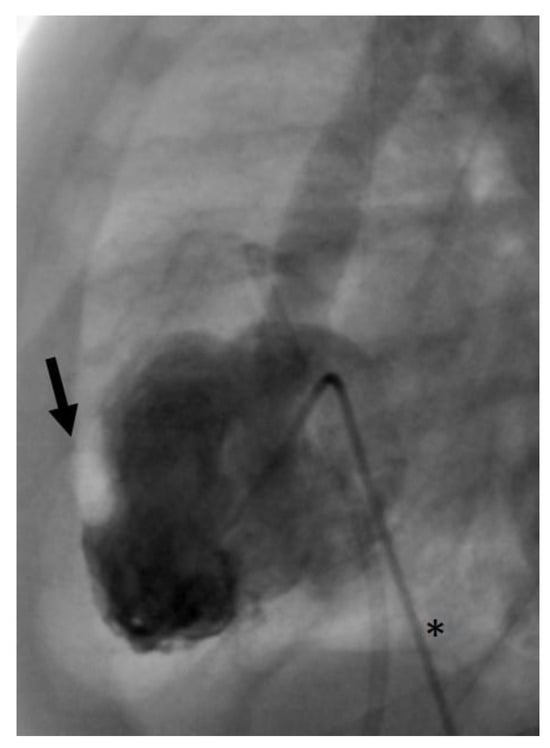

- In the same patient, an aortic wall injury resulting in a constriction of the intima following the second BAV occurred (Figure 9). However, this constriction was without significant stenosis and was corrected at the time of necessary aortic valve repair.